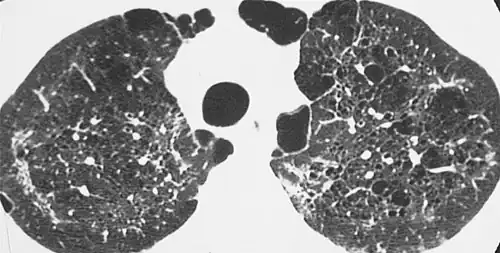

X-ray and CT of ground glass opacities and pneumothorax in pneumocystis pneumonia.[7]

Pneumothorax is a well-known complication of PCP.[8] Also, a condition similar to acute respiratory distress syndrome (ARDS) may occur in patients with severe Pneumocystis pneumonia, and such individuals may require intubation.[9]

The diagnosis can be confirmed by the characteristic appearance of the chest X-ray and an arterial oxygen level (PaO2) that is strikingly lower than would be expected from symptoms. Gallium 67 scans are also useful in the diagnosis. They are abnormal in about 90% of cases and are often positive before the chest X-ray becomes abnormal. Chest X-ray typically shows widespread pulmonary infiltrates. CT scan may show pulmonary cysts (not to be confused with the cyst-forms of the pathogen).